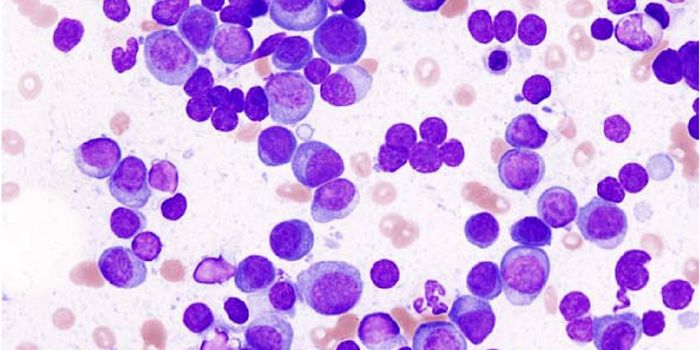

MAR 29, 2022Clinical & Molecular DXMyelodysplastic syndromes (MDS) describe cancers resulting from abnormal cells in the bone marrow. The abnormal bone mar ...

MAY 01, 2018CancerResearchers have developed a microfluidic device that can detect circulating plasma cells in whole blood; therefore, neg ...

JUN 08, 2016CancerResearchers at Lund University in Sweden recently announced the discovery of two new types of childhood blood cancers. T ...